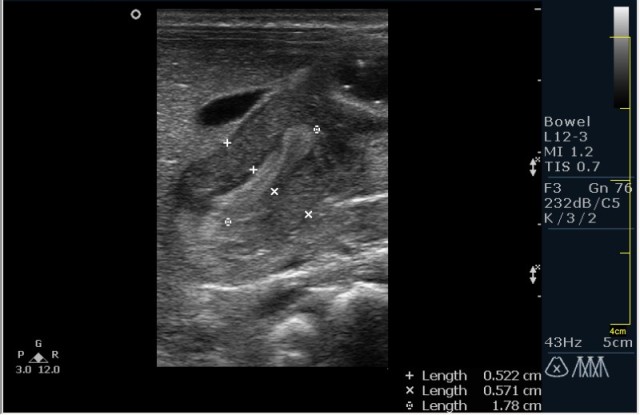

Ребёнок 1 месяц 10 дней от родy, с отсуствием прибавки в весе.

Hypertrophic pyloric stenosis.

Criteria:

1.Pyloric channel > 12 mm in length

2.Muscular layer thickness > 3-4 mm

3.Donuts sign at transverse scanning